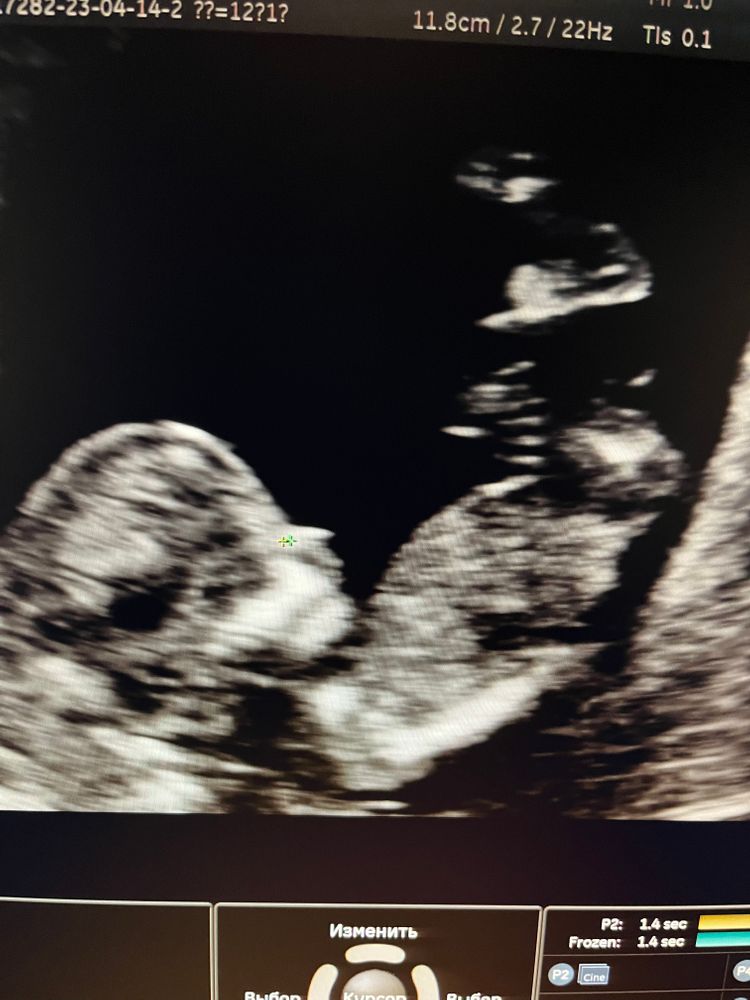

Наш малыш 🤰🎉

Беременность I триместр

Сегодня ходили на 1 скрининг , по результатам все хорошо!!! Теперь ждём анализы крови

Так хорошо уже виден человечек)

14.04.2023